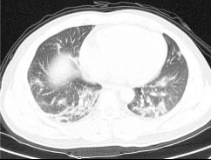

Table 3. Enhancement using dehazing and estimation of illumination for lung images of different datasets

Input Image

Output 1

Output 2

Final Enhanced Image

Lungs-1

Lungs-2

Lungs-3

Lungs-4

Note: This table is showing some lung images intermediate and final enhanced forms.

In Table 3, different dataset lung images' intermediate and final enhanced forms are showing. In the Table 4. we are showing the comparison between the calculated discrete entropy of enhanced images, PSNR, GMSD, and MCSD score for our proposed method as well as for Adaptive Gamma Correction with Weighting Distribution Method (AGCWD). In our proposed enhancement method, Entropy and GMSD score is always better than AGCWD method. High entropy is often desirable for images with complex textures and a lower value of GMSD indicates the improved quality of an image.